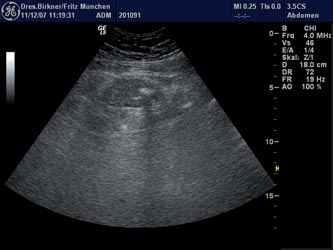

Im Darm können sich Ausbuchtungen der Darmwand (Divertikel) nach außen bilden, die in der Darmspiegelung als kleine Löcher zu erkennen sind (Bild Divertikulose). In seltenen Fällen können sich die Divertikel entzünden, dann spricht man von einer Dickdarmdivertikulitis. Die Diagnose wird durch die Symptome (Schmerzen), durch eine Bauchuntersuchung, eine Ultraschalluntersuchung (siehe Bild) und durch eine Laborunteruschung gestellt.